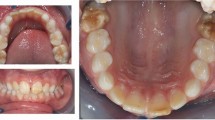

The term “Molar-Incisor Hypomineralization (MIH)” was first introduced by Weerheijm in 2001 [1] which refers to hypomineralization of systemic origin which occurs in one to four first permanent molars and frequently affects incisors as well [2]. Clinical presentations vary from demarcated opacities and enamel disintegration to atypical restorations and extracted teeth [3]. The most frequently-reported clinical issues associated with MIH include enamel surface breakdown, hypersensitivity, difficulties in achieving local anesthesia, behavioral management problems, anesthetic problems, tooth loss, eruption difficulties, negative impact on child’s school performance, and financial concerns [4].

There was substantial variation in reported MIH prevalence rates. Of the 13 studied geographical regions, the lowest prevalence of MIH was detected in Kerman [31] (5.14%) and the highest in Tehran [25] (%25.6). Kerman was the most studied region with prevalence rates of 6.5%, 8.4%, and 5.14% in three studies [23, 26, 31] Fig. 2.

In this systematic review, the lowest and highest prevalence rates were reported by studies conducted in Kerman (5.14%) [31] and Tehran (25.6%) [25] respectively. The second lowest prevalence was again reported by another study in Kerman (6.5%) [23]. The large variations may be explained by several factors such as ethnic and environmental variations and methodological differences. Although almost all studies used the same EAPD diagnostic criteria, two studies used DEE [18, 22] and one used a combination of EAPD and mDDE criteria [32]. The operator dependency of visual diagnosis may also contribute to variations. Probably due to the same mentioned reasons, reported prevalence of MIH across the globe shows a wide variation (2.4–40.2%) as well [22].